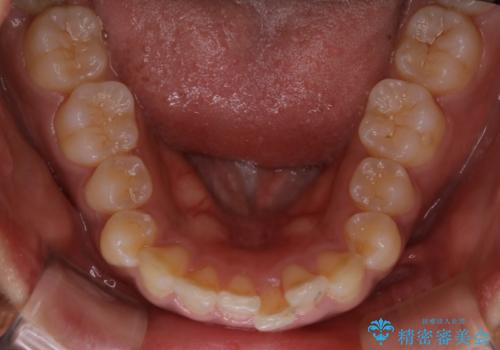

インビザライン矯正 歯を抜かずに出っ歯を改善!

- 出っ歯と前歯の隙間が空いていることを気にされて来院されました。

また、自然な感じで口元を下げていとのことでした。

奥歯のかみ合わせが問題なかったため、上顎の前歯の隙間を閉じるとともに、上顎の歯の側面を削ることをメインにして、出っ歯を改善する治療計画としました。

上顎の歯の傾きを変えるうえで、下顎の歯とのバランスのことも考え、下顎の歯の側面も削ることを加えています。

また、今回は口元を変えたい中に、劇的な変化は避けたいとのことだったので、抜歯をしない計画としています。

抜歯をしない場合、口元の変化は感じにくいですが、前歯の傾きが変わることで、口の閉じやすさは感じていただけたとのことです。

症例にもよりますが、本症例は奥歯のかみ合わせに問題がなかったので歯の側面を削ることメインに、前歯の傾きを改善することができました。

抜歯を行う場合や抜歯をしなくても奥歯の位置をずらす場合は、治療期間が長期化することが多いですが、今回は歯を削ることで改善できたため、短期間で治療を完了することができました。